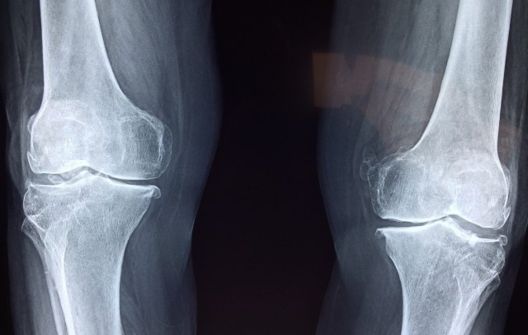

5. Kosti će vam ojačati

Bilo kakva aktivnost u kojoj su kosti pod pritiskom težine tijela pridonosi jačanju kostiju i smanjuje rizik od osteoporoze. To se događa zbog toga što se kosti pri nošenju težine tijela više naprežu i na taj način jačaju. Takav pritisak na kosti također potiče stvaranje novih stanica u kostima.